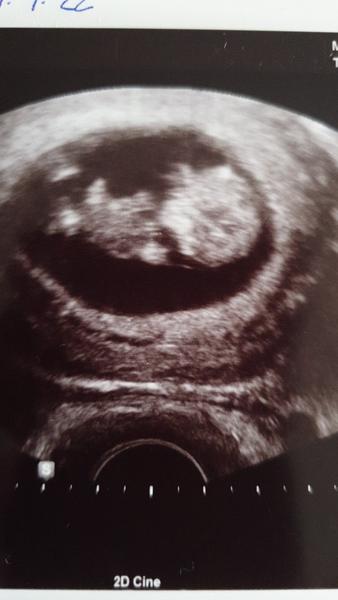

Ahoj holky, jdu se tady k vám přidat, momentálně jsem 7+4tt s dvojčátky. Zvládli jsme dvou týdenní krvácení z hematomu a v pondělí jsem byla naposled na kontrole a bobišci jsou oba stejně velcí a hezky jim bijí srdíčka 🥰 jsem od 5+5tt na nemocenské, kvůli predeslym potratum a tomu krvácení 🙂 na fotku se vždy jeden schoval 🥰